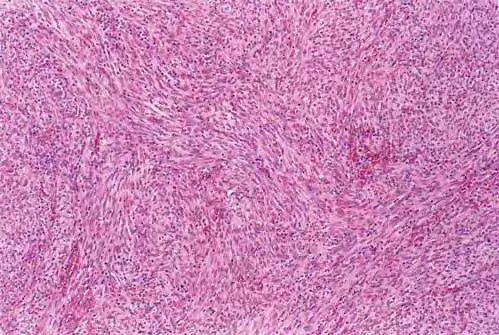

HISTOPATHOLOGY

The histopathology of KS is dependent on the stage of KS development. Early patch-like lesions exhibit rather discrete histopathologic changes, consisting mainly of an increase in the number of dermal vessels, outlined by slightly irregular endothelial cells (Fig. 128-5). These vessels, located mainly in the superficial dermis are parallel to the skin surface, are frequently slightly irregular, and may form bizarre slits and clefts. In the surrounding skin focal hemosiderin, deposits and extravasated erythrocytes can be found as well as a moderate inflammatory infiltrate. Important differential diagnoses of this stage include lymphangioma and granulation tissue.

The pathology of KS plaques is more characteristic and reveals extensive vascular proliferation at all levels of the dermis with multiple dilated and angulated vascular spaces dissecting the collagen leaving a spongy network of collagen tissue. A characteristic sign of KS papules is the presence of solid cords and fascicles of spindle cells arranged between the jagged vascular channels. This biphasic angiomatous and solid tumor morphology changes to a clear-cut sarcomatous morphology with progression of the disease.

Nodular lesions consist predominantly of spindle cells arranged in bundles and interlacing fascicles and interspersed, irregular, slit-like vascular spaces without endothelial linings. Advanced lesions may display pronounced pleomorphism, nuclear atypia, and mitotic figures. At the periphery of solid tumors, (lymph) angiomatous-like portions of KS with bizarre vascular lumina and intravascular and extravasated erythrocytes, as well as siderophages, may be preserved. Erythrocytes, which appear as eosinophilic globules, are trapped within the slits and clefts formed by the spindle cells and erythrophagocytosis are occasionally observed. As in all other stages of KS, a moderate inflammatory infiltrate consisting of lymphocytes, histiocytes, plasma cells, and, sporadically, neutrophils is regularly present.